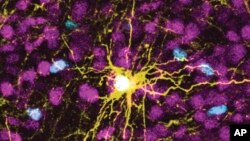

This microscope image provided by Pasca Lab/Stanford Medicine shows a human astrocyte cell, center in yellow, and human glial cells (scattered in blue) inside the brain of a rat.

นักวิทยาศาสตร์กลุ่มหนึ่งทำการทดลองปลูกถ่ายเซลล์สมองของมนุษย์เข้าไปในสมองของหนูเกิดใหม่ เพื่อให้เซลล์เหล่านี้สามารถเจริญเติบโตและสร้างการเชื่อมโยงกับระบบประสาทได้ โดยการวิจัยนี้เป็นส่วนหนึ่งของความพยายามที่จะศึกษาพัฒนาการทางสมองของมนุษย์และโรคภัยไข้เจ็บต่าง ๆ ที่ส่งผลต่ออวัยวะที่มีความซับซ้อนที่สุดนี้

ในการสร้างสมองเลียนแบบมนุษย์นั้น นักวิทยาศาสตร์ของมหาวิทยาลัยสแตนฟอร์ดได้เปลี่ยนเซลล์ผิวหนังของมนุษย์ให้เป็นเซลล์ต้นกำเนิด จากนั้นจึงทำให้เซลล์ต้นกำเนิดกลายเป็นเซลล์สมองหลาย ๆ ชนิด โดยเซลล์เหล่านั้นจะมีจำนวนเพิ่มขึ้นเพื่อสร้างสิ่งที่คล้ายกับเปลือกสมอง ซึ่งเป็นชั้นนอกสุดของสมองมนุษย์ และเป็นส่วนที่เชื่อมกับความจำ การคิด การเรียนรู้ การใช้เหตุผล และอารมณ์ของคนเราด้วย

นักวิทยาศาสตร์ได้ปลูกถ่ายเซลล์สมองเหล่านี้ในลูกหนูที่อายุสองถึงสามวัน ซึ่งเป็นช่วงอายุที่การเชื่อมต่อของสมองยังคงก่อตัวอยู่ และเซลล์สมองดังกล่าวจะเติบโตจนในที่สุดพวกมันก็ครอบครองหนึ่งในสามของซีกสมองของหนูที่มีการปลูกถ่ายไว้ โดยเซลล์ประสาทจากเซลล์สมองที่ก่อตัวขึ้นยังจะสร้างความเชื่อมโยงกับสมองอีกด้วย